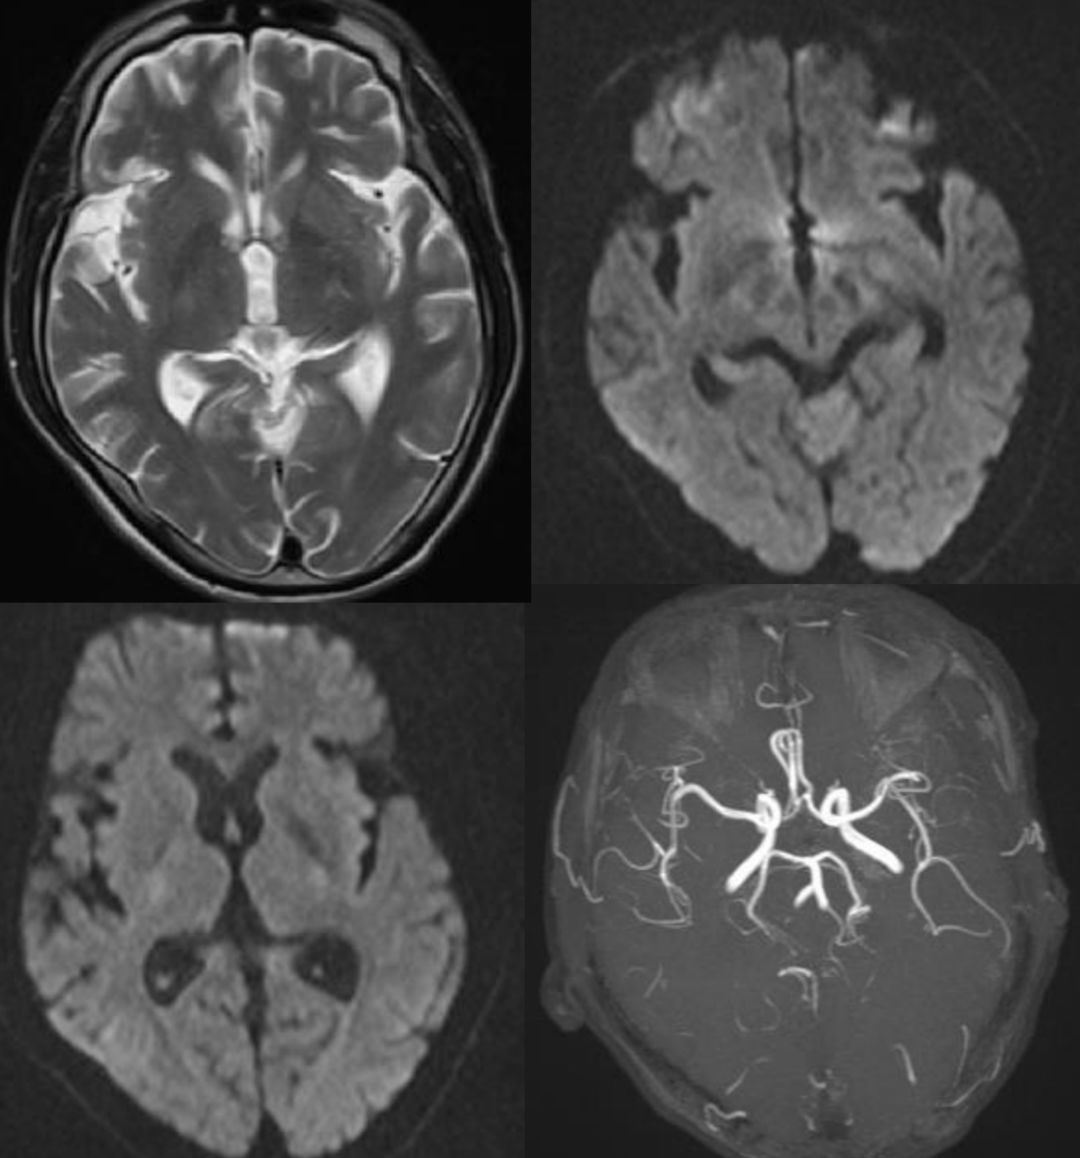

患者,21岁女性,患者3小时前做某手术后突 发右侧肢体乏力、意识不清。

发病24小时磁共振:

答案:脑型脂肪栓塞综合征。患者做了自体脂肪填充术。脂肪栓塞综合征(fat embolism syndrom,FES)是指直径为10~40μm的血管内脂肪颗粒阻塞血管腔而引起的一系列病理生理改变的临床综合征。FES常发生于骨创伤及骨手术病人。FES潜伏期为6~24h,FES 的典型三联征为低氧血症、意识障碍和瘀斑。